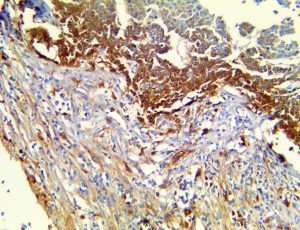

The first cytokines released are interleukin 1β (IL-1β) and tumor necrosis factor-α (TNF-α), which attract a variety of circulating white blood cells (WBCs) to the infection site, including neutrophils, monocytes, macrophages, and natural killer (NK) cells. This response, along with the antipathogenic chemicals released by these cells (i.e., complement), comprise the innate immune response. These cells directly attack the invading pathogen and also release additional cytokines, chief among them interleukin-1 and 6 (IL-6). IL-6 is essential for invoking the adaptive immune response, which calls T-cells, B-cells, and T helper (Th) cells to the infection site. IL-6 also stimulates further recruitment, proliferation and activation of macrophages.

This activation induces inflammatory monocytes to highly express IL-6, starting a localized and then systemic cascade effect that results in hyperproduction of IL-6, which accelerates the inflammatory process. Because IL-6 also increases vascular permeability, excessive levels cause blood vessels to become very leaky. This, along with clotting factors released from vascular endothelial cells, stimulates the coagulation cascade, resulting in microthrombosis (tiny clots), which leads to ischemia and tissue death of the kidney, intestines, heart, liver, brain and extremities.